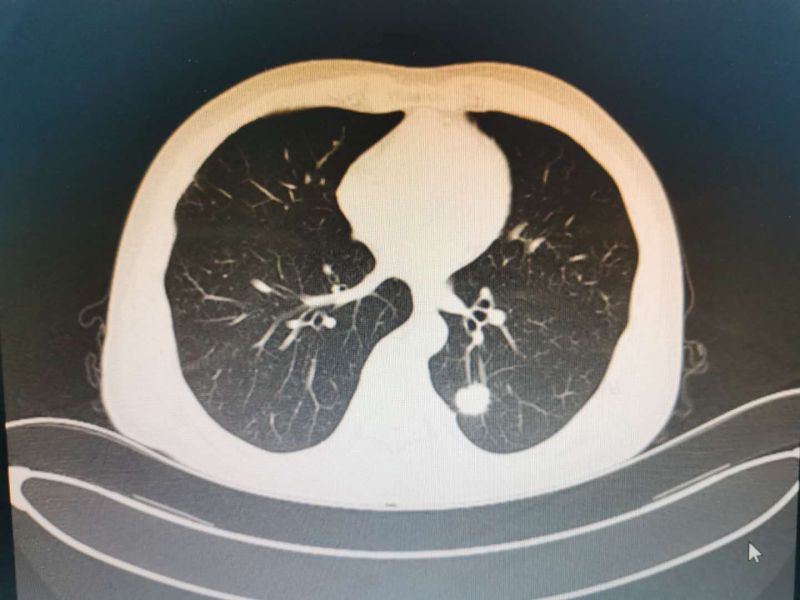

患者男性,51岁,因“反复胸闷”入我院心血管内科住院治疗,完善检查发下左下肺占位,经我科医师会诊后考虑“左下肺占位:恶性肿瘤可能性大”建议积极手术治疗。转入我科后予积极完善术前检查,经充分术前准备及术前讨论评估后在黄勇科主任为首的心胸外科团队努力下成功实施了单操作孔VATS下左下肺叶切除术并进行了系统淋巴结清扫,手术非常顺利,出血甚微。

患者CT影像学表现

据了解,肺癌是起源于肺部支气管黏膜或腺体的恶性肿瘤,是发病率和死亡率增长最快,对人群健康和生命威胁最大的恶性肿瘤之一。早诊断、早治疗是提高肺癌患者生存率的最好办法。中晚期肺癌患者远期生存率较低,而早期肺癌手术切除患者10年预期生存率达88%以上。近年来低剂量螺旋CT的普及,发现了诸多肺部小结节患者,而小部分肺部小结节有可能是早期肺腺癌(原位癌、微浸润及浸润性腺癌),早期肺腺癌的CT表现为磨玻璃、亚实性、混合性结节样病变,通过手术治疗其5年无病生存期更接近100%,基本可达临床治愈目的